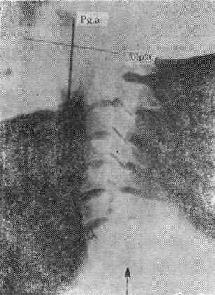

(三)呼吸道异物吸入较大的食团卡阻在喉部,所谓“咖啡馆冠心症”是众所周知的急症,特别是老人(图113-2)。①由于酒精或药物的中毒致会厌的反射和知觉障碍而吸入食物;②义齿牙托随食物吸入;③未嚼研讨会的食团吸入,最常见的是肉块,在儿童最常见者是花生米、豆粒、瓜子等。食管异物压迫侵犯气道而进入气管。

片中示较大的食团卡在喉部

图113-2 片中示较大的食团卡在喉部